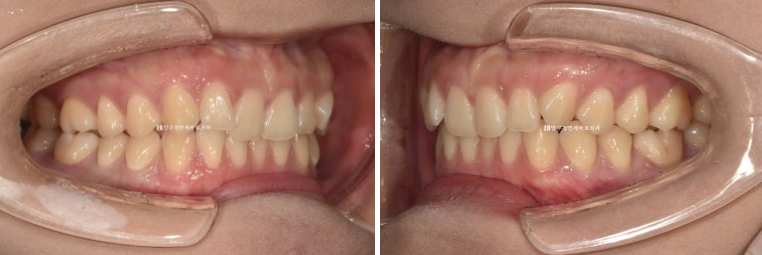

24.02~24.11

문제의 우측 II급 교합관계가 거의 I급으로 좋아졌습니다.

고무줄을 열심히 껴준 덕입니다.

좌측교합은 원래 I급이고 위아래 어금니 교합이 좀 더 긴밀해졌습니다.